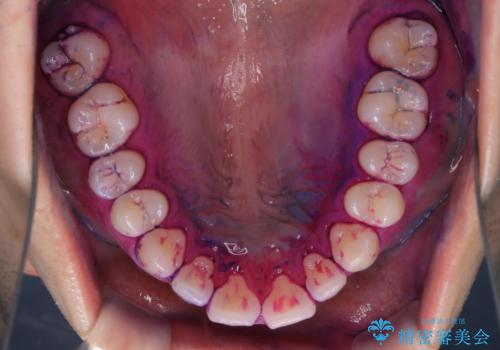

親知らずを抜いて1週間後にPMTC 歯のクリーニング

- 親知らずの抜歯後の約1週間後に抜糸(縫った部分の糸とり)で来院されました。その際、抜歯後は傷口が怖くて歯磨きが上手くできず、汚れや口臭が気になるためクリーニングも希望されました。

抜歯後は多少出血したり、違和感や痛みを感じたりすることがあります。そのため親知らずを抜いたり、外科的な処置をするといつも通りの歯磨きがしづらくなります。また、傷口の周りが心配で、歯ブラシをするのが怖くなるものです。抜歯後落ち着いたら、歯科医院にて専門の機械を使用しクリーニングをすることがおすすめです。抜歯前や後にPMTCを行うことで、お口の中の健康維持につながり、その後の感染・腫れ・口臭予防などになります。

親知らず抜歯後正常に治癒が進んでいれば1週間後から可能です。